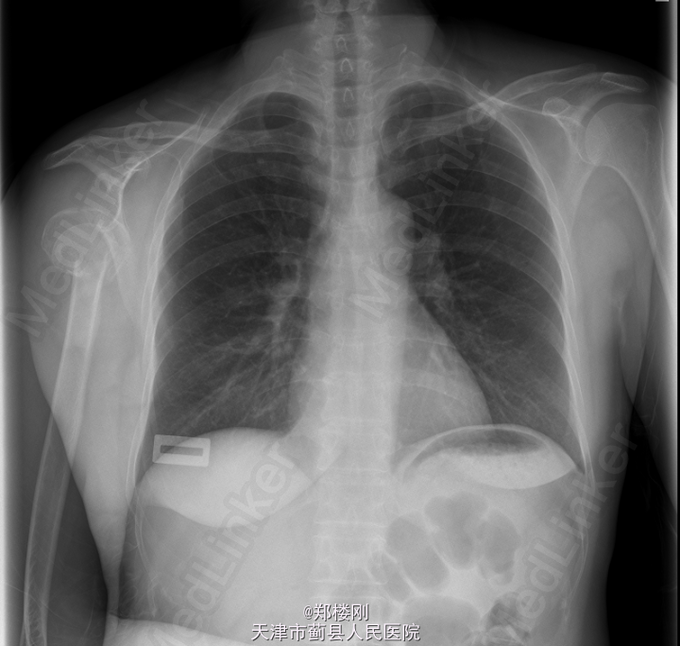

患者,女,52岁,因“摔伤致右上臂疼痛伴活动障碍1天 ”入院。

查体:右手散在皮肤挫伤,右肩部肿胀明显,主动活动受限,远端皮肤感觉无殊,肢端动脉搏动存在,右手活动可,左上臂及双下肢无殊。未引出病理反射。辅助检查:2015-04-29 当地医院X线示:右肱骨近端骨折。我院CT(右上肢)检查提示:右侧肱骨外科颈骨折,断端嵌插,周围见较多碎骨片影;右侧股骨头向下脱位;右侧肩关节少许积液,周围软组织肿胀。